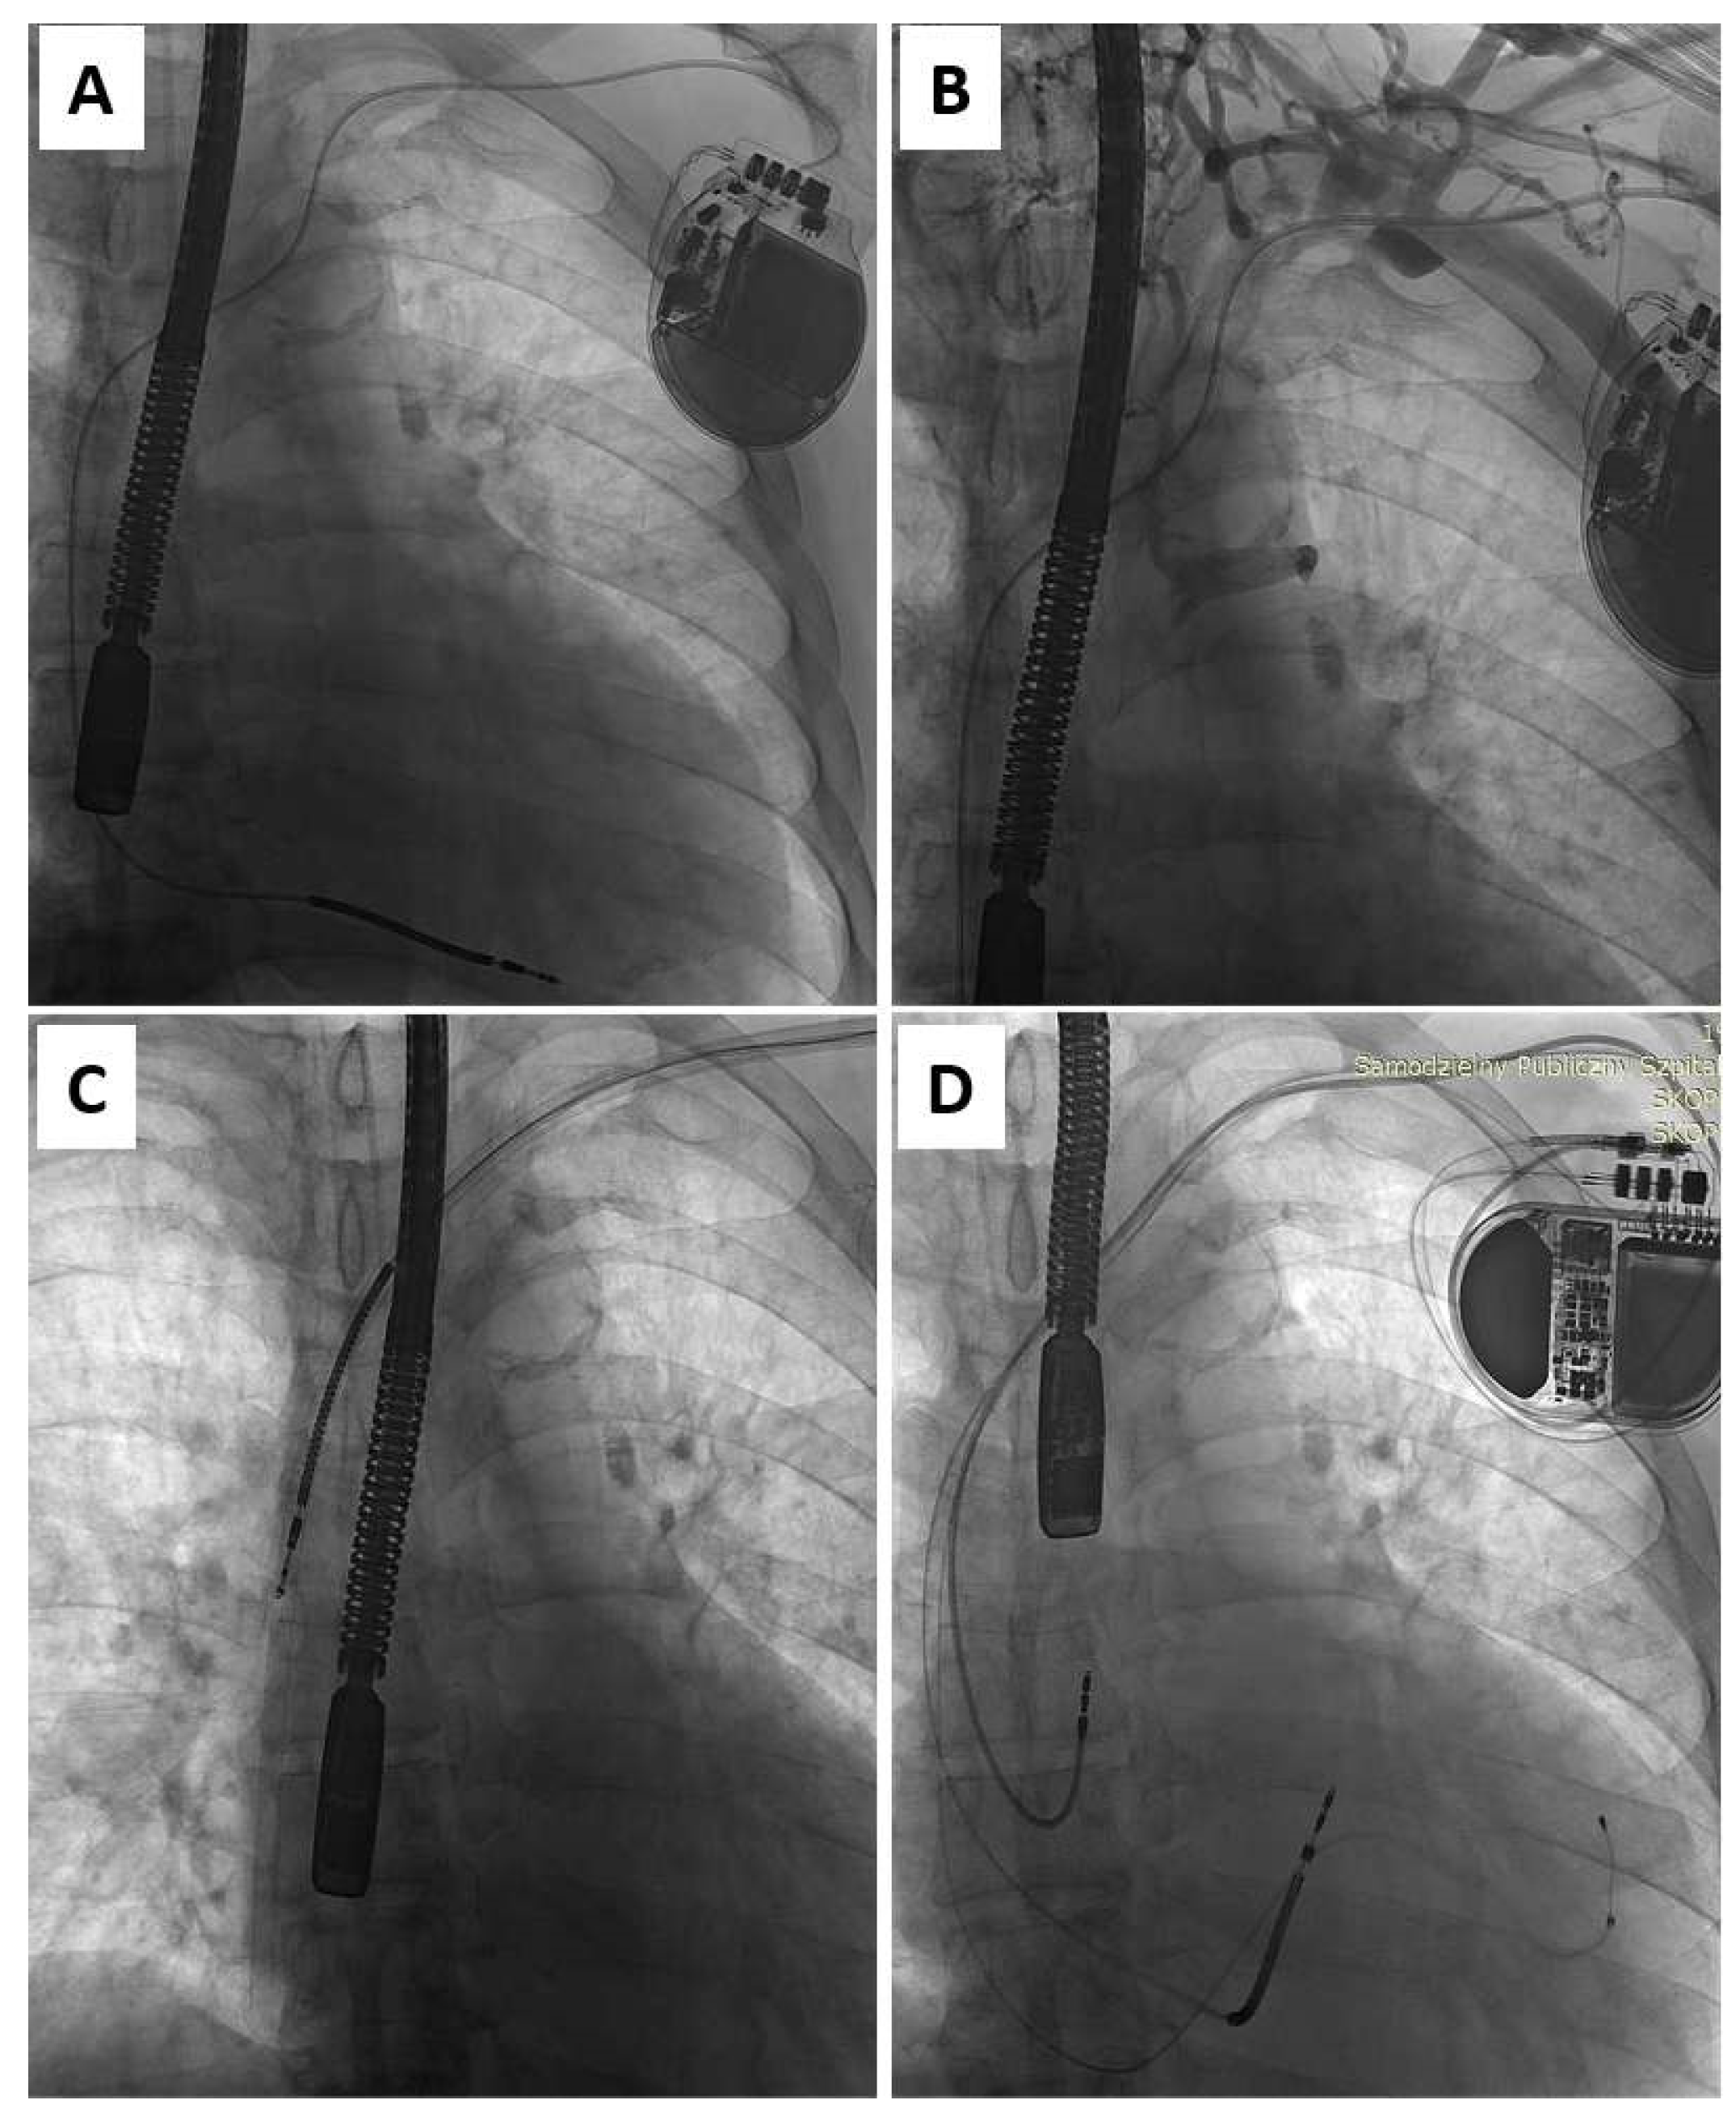

Figure 1.

Upgrade from ICD-V (A) to CRT-D in the patient undergoing TLE for lead-related venous obstruction (B). Moving the introducer sheath over the lead to the heart facilitates not only the removal of the lead (C) but also reestablishing access for the implantation of three new leads (D).